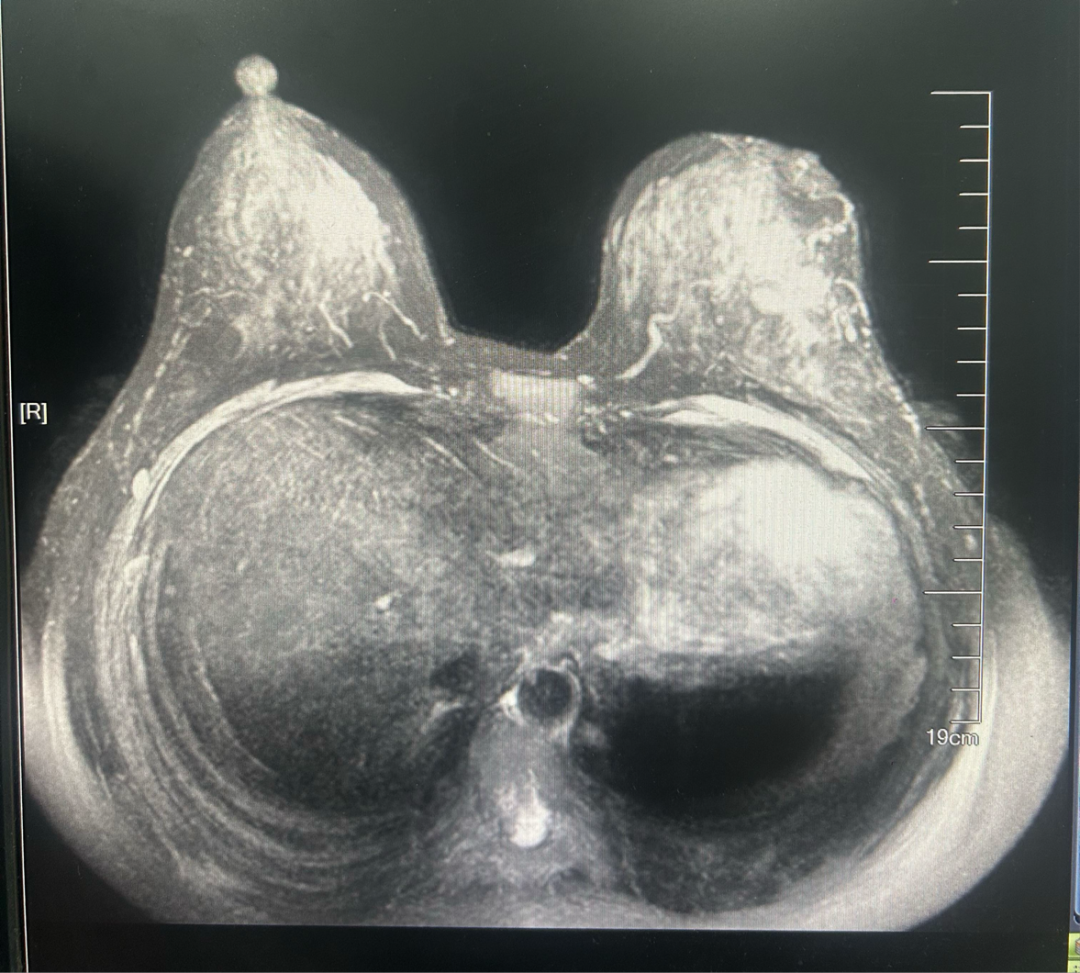

·乳腺彩超

2023-06-26彩色多普勒超声宽景成像+术前体表定位:

1、左乳4点钟方向实性肿块(乳腺Ca可能,BI-RADS 4C类),已体表定位,此次定位仅供手术医生参考。

2、双乳乳腺增生症。

3、双侧腋窝探及多个淋巴结。

图1.2023年6月24日乳腺彩超